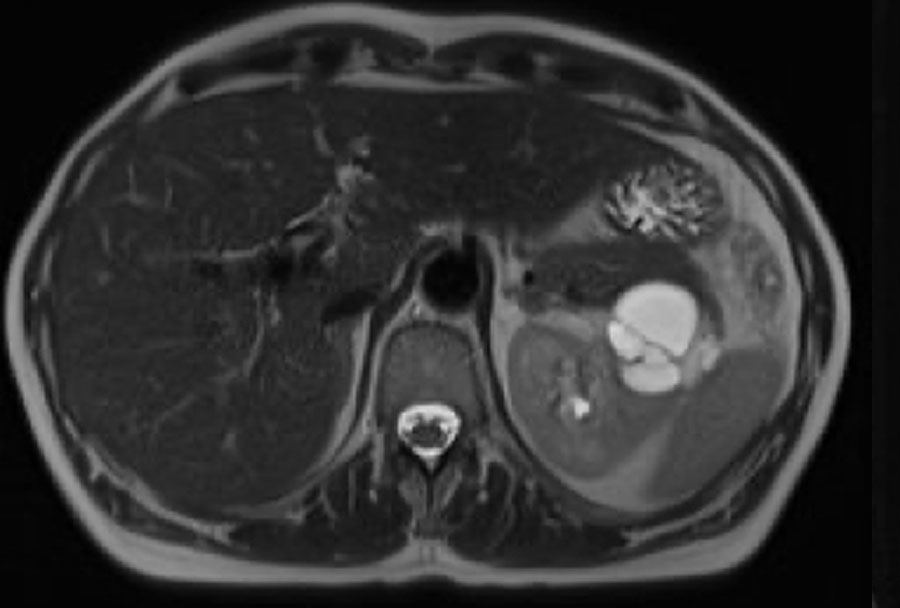

Các ảnh T2W mặt phẳng axial và coronal cho thấy một tổn thương dạng nang ở cực dưới thận trái với thành dày không đều.

Do thành phần mô đặc chiếm dưới 25% tổn thương, tổn thương cần được phân loại là khối dạng nang thay vì u thận đặc dạng nang.

Trên các ảnh T1W coronal có ức chế mỡ trước và sau tiêm thuốc tương phản từ, độ dày thành đo được trên 4 mm (mũi tên).

Tổn thương được phân loại là khối dạng nang Bosniak IV.

Khối đã được phẫu thuật cắt bỏ và được xác nhận là ung thư biểu mô tế bào sáng.